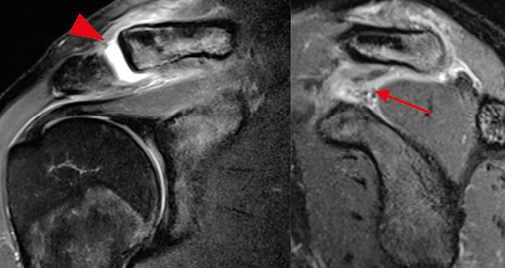

Rééducation La butée d'épaule sous arthroscopie : exemple d'une collaboration renforcée chirurgien-kinésithérapeute